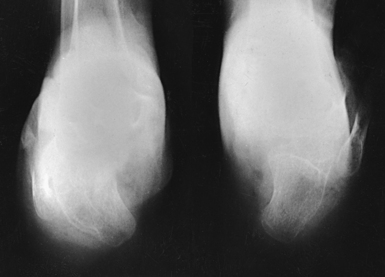

The typical clubfoot, or talipes equinovarus, shows three deviations from the normal alignment of the foot in relation to the weight-bearing axis of the leg. These deviations are plantar flexion and inversion of the calcaneus (equinus), medial displacement of the forefoot (adduction), and elevation of the medial border of the foot (supination). The typical clubfoot has numerous variations. Each of the typical abnormalities just described has varying degrees of deformity.

The classic Kite methods12—exactly placed AP and lateral projections—for radiography of the clubfoot are used to show the anatomy of the foot and the bones or ossification centers of the tarsals and their relation to one another. A primary objective makes it essential that no attempt be made to change the abnormal alignment of the foot when placing it on the IR. Davis and Hatt3 stated that even slight rotation of the foot can result in marked alteration in the radiographically projected relation of the ossification centers.

The AP projection shows the degree of adduction of the forefoot and the degree of inversion of the calcaneus.

• Rest the feet flat on the IR with the ankles extended slightly to prevent superimposition of the leg shadow.

• Hold the infant’s knees together or in such a way that the legs are exactly vertical (i.e., so that they do not lean medially or laterally).

• Using a lead glove, hold the infant’s toes. When the adduction deformity is too great to permit correct placement of the legs and feet for bilateral images without overlap of the feet, they must be examined separately (Figs. 6-64 and 6-65).

• Perpendicular to the tarsals, midway between the tarsal areas for a bilateral projection

• An approximately 15-degree posterior angle is generally required for the central ray to be perpendicular to the tarsals.

• Kite12 stressed the importance of directing the central ray vertically for the purpose of projecting the true relationship of the bones and ossification centers.

The Kite method lateral radiograph shows the anterior talar subluxation and the degree of plantar flexion (equinus).